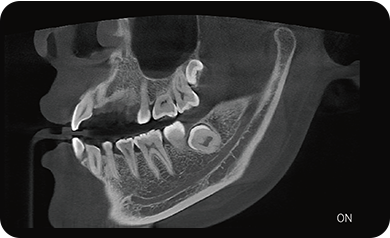

支持局部超清三维显示

局部超清显示、 移动视野摄片

可根据临床需求任意调整成像区域大小实现局部超清三维显示

临床样片